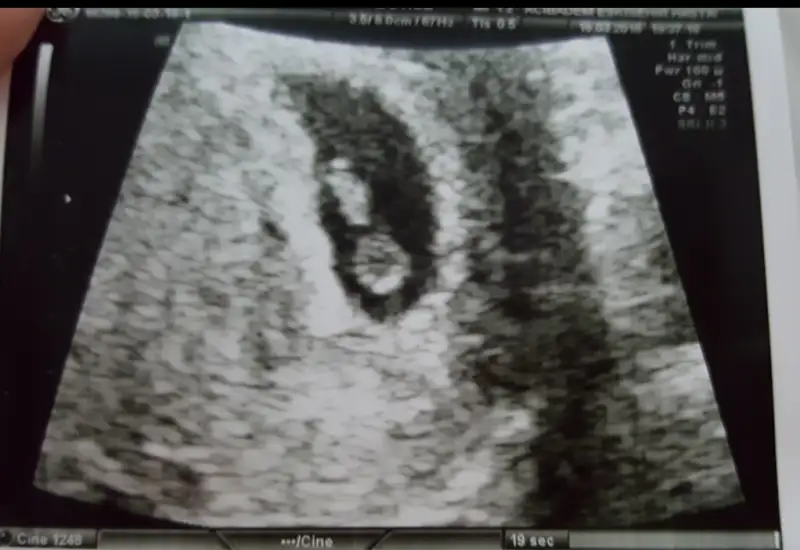

İlk bebişin mi canım. Ben doktoruma direkt sordum. karından ultrasonda plasentasi solda görünüyorsa gerçekte sagda imiş. Usg vajinal ise plasenta diyelim ki solda görünüyor gerçekte de solda imiş. Bende bu teori tutmadı canım. Ama tutan çok fazla hamile var. Benim iki oglumunda plasentasi soldaydı. Plasentanın gerçekte solda olması kız bebek demek.bhchrk cnm sende istersen koy goruntuyu bakalim sana ne dicekler :) bana kiz dedi

Ilk benek olcak hayirlisiyla cnm :) bu plesenta dedigin benim gonderdigim resimde alt tarafta parlak olan sey mi oluoİlk bebişin mi canım. Ben doktoruma direkt sordum. karından ultrasonda plasentasi solda görünüyorsa gerçekte sagda imiş. Usg vajinal ise plasenta diyelim ki solda görünüyor gerçekte de solda imiş. Bende bu teori tutmadı canım. Ama tutan çok fazla hamile var. Benim iki oglumunda plasentasi soldaydı. Plasentanın gerçekte solda olması kız bebek demek.

Ben sağ üstte gibi gördüm canım. Yanılıyor olabilirim tabi kiIlk benek olcak hayirlisiyla cnm :) bu plesenta dedigin benim gonderdigim resimde alt tarafta parlak olan sey mi oluo

kizlar bu da minnagiimm :)) ustteki minnagiimm alttaki yolk kesemizz :)) sizce cinsiyeti ne olabilir :))

karindan bakildi vala ben de erkek hissediyorum :))) hayirli evlat olsun daa insallah hayirlisiylaa :)))Usg karındansa erkek gibi,vajinalsa kız gibi

Benimkini bi de sen yorumlar misiiiinnn :) karindan ultrasonUsg karındansa erkek gibi,vajinalsa kız gibi

Benimkini bi de sen yorumlar misiiiinnn :) karindan ultrason